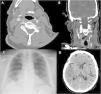

Paciente 6. A) Angio-TC axial, trombo endoluminal sobre placa de ateroma en la arteria carótida interna derecha (ACI).B) Reconstrucción coronal de angio-TC, placa de ateroma calcificada y trombo endoluminal sobre placa C) Radiografía de tórax,infiltración difusa bilateral por COVID-19. D) TC de cráneo sin contraste, con signos de infarto cerebral en el territorio de la ACMderecha.